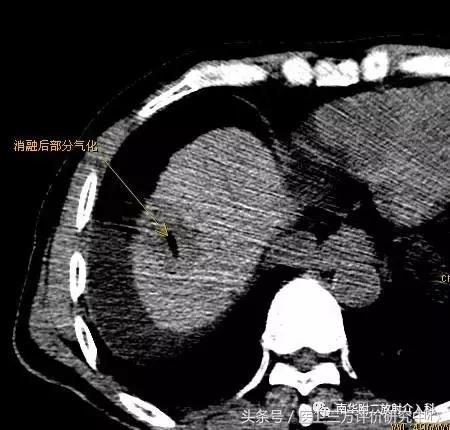

微波消融后局部改变(肿瘤坏死、气化)